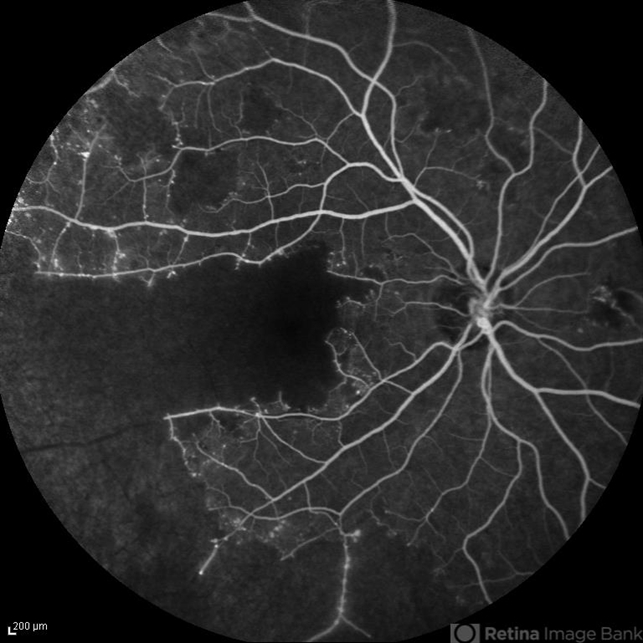

- capillary closure, macular infarction

- Solmaz Shahmohammad, Negah Eye Center, Tehran

- Heidelberg Spectralis

- Late phase FA image of the right eye of a 28-year-old woman with idiopathic occlusive retinal vasculitis 6 months after the onset.